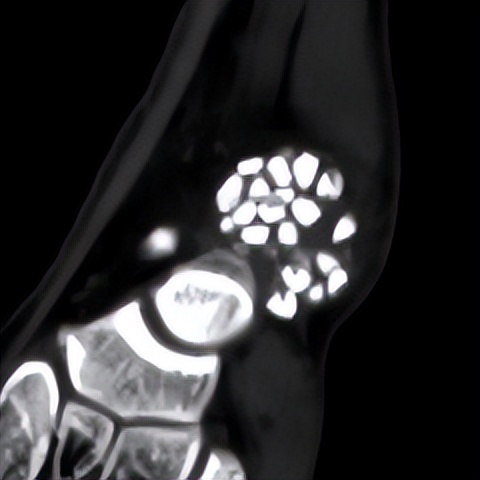

何河北制定了详细的手术方案,为患者开展踝关节镜下滑膜软骨瘤取出术+距腓前韧带重建术。他从患者踝关节中取出32颗“珍珠”(关节游离体),然后进行踝关节外侧韧带重建。

▲术中取出31颗滑膜软骨瘤。